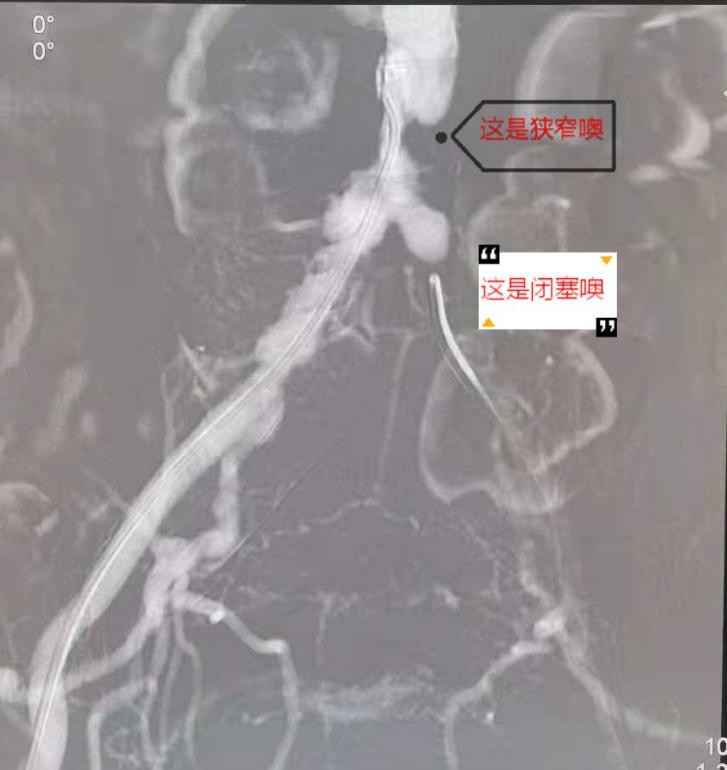

5月17日下午,心脏大血管外科副主任医师唐开维与科室副主任轩永波顺利为老张完成了手术。术中造影提示老张左髂总动脉闭塞,局部多发斑块,无血流通过。腹主动脉下段狭窄约80%,右髂总动脉中上段有斑块,造成局部狭窄50- 60%,左髂总动脉起始部后闭塞。老张病情复杂,两位专家先从左侧多次尝试使导丝导管突破闭塞段,最后成功突破进入腹主动脉真腔内。考虑老张局部动脉斑块多,为预防破裂,他们进行逐级扩张,定位良好后释放支架。为处理老张腹主动脉下段狭窄的问题,他们沿左侧、右侧导丝同时送入血管支架,使用Kissing技术成功释放两枚支架。手术很成功,再次造影时显示老张体内支架位置良好,其内血流通畅,支架无明显狭窄。

术中造影显示狭窄和闭塞的血管